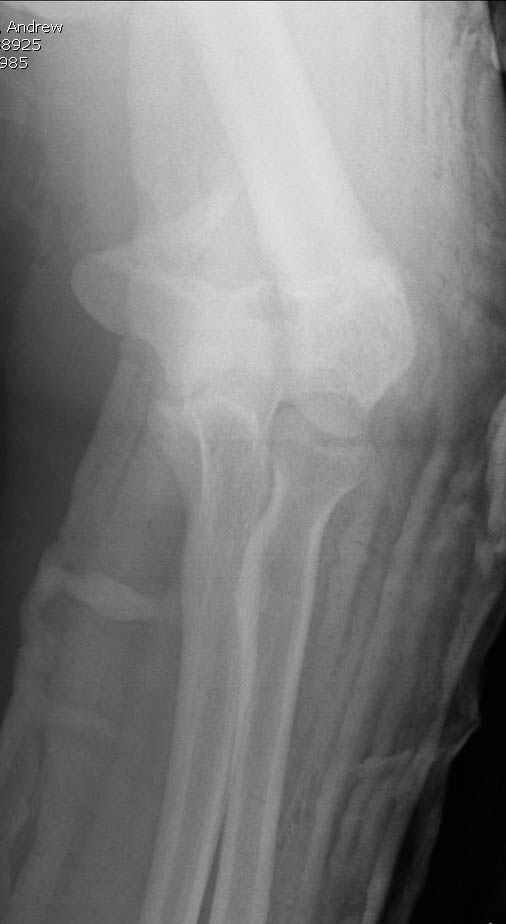

Уважаемые коллеги! Мужчина, 28 лет. 1 сутки назад получил бытовую травму - закрытый чрезмыщелковый перелом правой плечевой кости со смещением. По месту жительства в ЦРБ - репозиция, иммобилизация. Направлен к нам.

Место болезни без особенностей, неврологических и сосудистых расстройств нет. Принято решение об оперативном лечении - чрескостный остеосинтез.Предложения по конструкции АВФ (т.к. мнения расходятся)? Заранее благодарю! С уважением,А.В.ВладзимирскийДонецкий НИИ травматологии и ортопедииДонецк, Украина

Солидарен с мнением обоих Александров (Челнокова и Рыкова): точную репозицию такого перелома вряд ли удастся выполнить закрыто. Даже во время открытого вмешательства это сделать непросто. Неслучайно предложен костно-пластический доступ с временным отсечением локтевого отростка. И по методу фиксации согласен с Александром Челноковым: 2 пластины. В качестве примера привожу рентгенограммы одного из наших пациентов с аналогичным повреждением.

С уважением, А. Золотов, Приморский край.